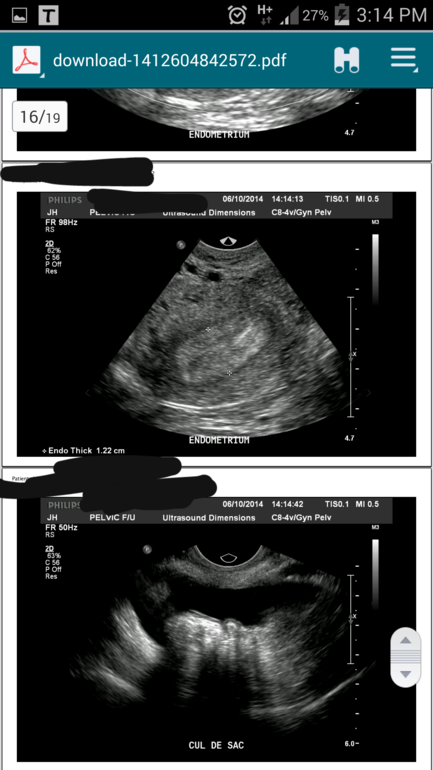

Эндометрий и жидкость

Да она есть,именно я правой стороны гле и Дф был... значит думаете что фоллик лопнул, и желтое тело переросло в кисту Жт!? Эндометрий еще 1.22см